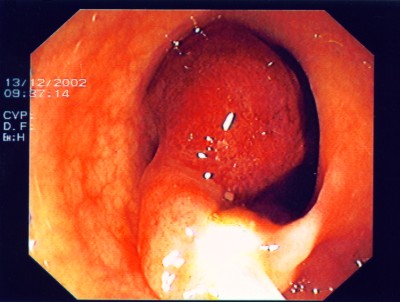

Wie bei den Abbildungen 28 und 30 handelt es sich um einen breitbasigen, relativ flachen, noch nicht entarteten Polyp, der sich mit einer Schlinge nicht vollständig abtragen ließe.

Wie bei den Abbildungen 29 und 31 erfolgt hier nach einem speziellen kombinierten Manöver (laparasko typisch gestützte Koloskopie - gleichzeitige Bauch- und Darmspiegelung), Entfernung des Polypen weit im Gesunden mit einem speziellen Klammernahtgerät. Die hier gut abgebildete Klammernahtreihe bleibt zurück. Der Eingriff erfolgt - wie gesagt - in so genannter Schlüssellochtechnik, aber auch mit unterstützender Darmspiegelung.